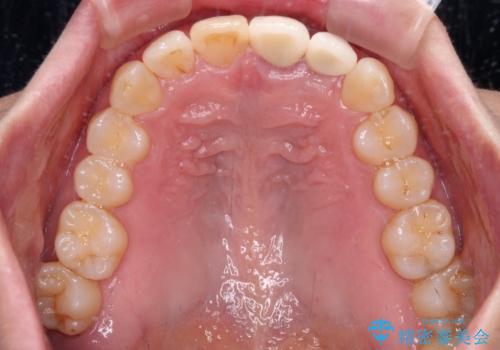

- 下顎前歯が抜けそうとのことで来院された患者様です。

初診の状態ではすぐにでも抜けそうな状態で、インプラントによる補綴治療を行うこととしました。

インプラント治療に際し、前歯の叢生に対する矯正治療を提案したところ、興味を持たれたので、インビザライン・ライトによる矯正治療を行うこととしました。

抜歯後にスペースができると恥ずかしいため、抜歯した歯を接着剤で固定した上で矯正治療を行い、その後インプラントやオールセラミッククラウンの装着を行うこととしました。